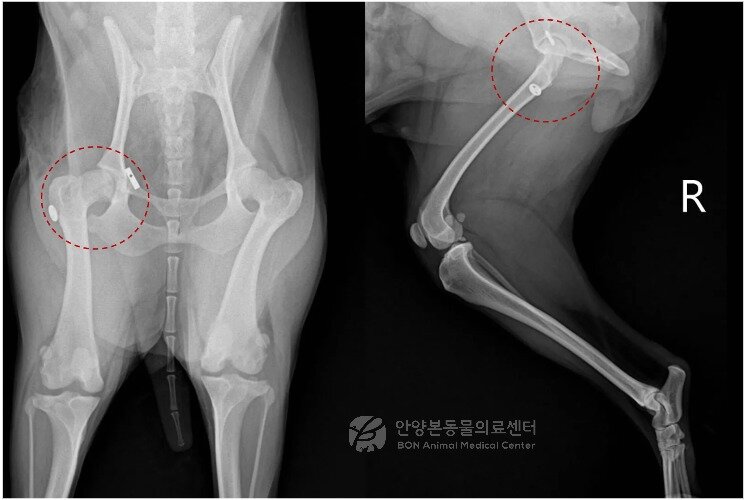

본문 이미지 - 수술 후 방사선 검사 결과(본동물의료센터 제공) ⓒ 뉴스1

수술 후 방사선 검사 결과(본동물의료센터 제공) ⓒ 뉴스1